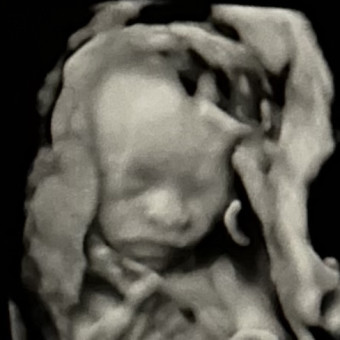

Hi family and friends, here is our registry for our baby girl Daiya Bell💘